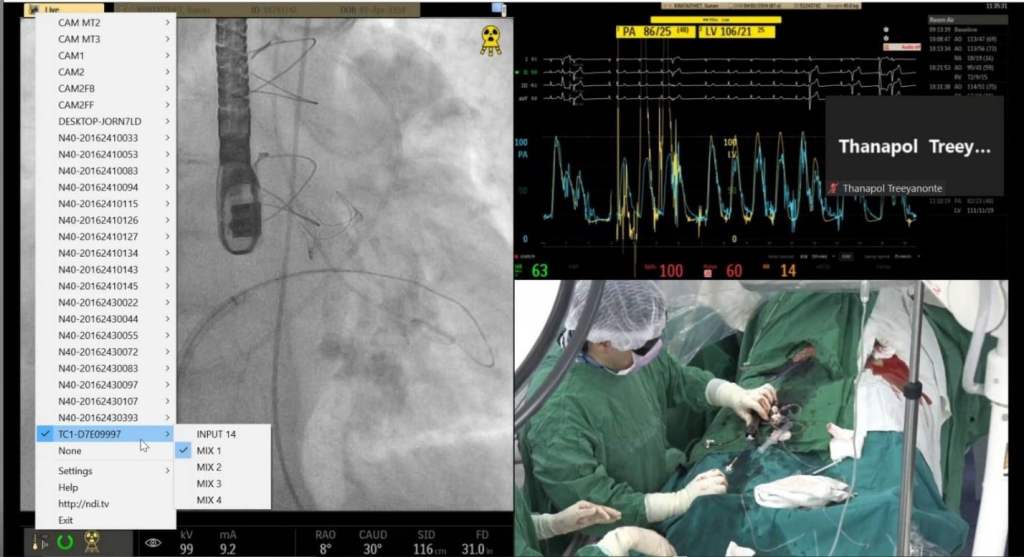

The Hospital has since discovered a completely different approach that enables live video from cameras in the operating rooms to be showcased and streamed, along with readings from the wide array of medical devices simultaneously in use during surgical procedures. Unlike the conference setup, this solution is based upon Vizrt live video production and streaming solutions, such as the TriCasterĀ® TC1 and TriCaster Mini 4K. These easy-to-use video creation systems let anyoneāeven those lacking specialized video production or IT expertiseāproduce compelling videos with broadcast-quality results and resolutions up to UHD.

Adding to the user-friendliness of the Vizrt gear is their full support for Network Device Interface (NDIĀ®), an industry standard Video-over-IP networking protocol. NDI enables video transport in real-time over standard gigabit ethernet local area network cabling, the type thatās commonly available at facilities like those at the Hospital. Vizrt video production and streaming solutions work together with NDI to make it relatively simple and cost-effective to produce high-quality video with just a single operator or small video crew. The equipment was purchased from SWS Group Company Limited, a video dealer in Bangkok, Thailand.

With its unique video production setup, the Hospital has strategically positioned NDI-compatible video cameras around two of its operating rooms, with plans to outfit a third in the near future. Using an iPad, laptop, or computer keyboard, video signals from the NDI cameras can be pre-set, controlled, switched, and displayed in the facilityās conference room or incorporated into online meetings via platforms such as Zoom. The video signals can just stream into the TriCaster switchers, or these IP-based tools allow remote control of the cameras, including the pan, tilt, zoom functions, if desired. This is part of their Livestreaming Cardiac Training and Consultations initiative in the Thai hospital.

Data from the medical devices in the OR can also be managed and controlled remotely using the iPad, laptop, or computer interface. The HDMI and DVI outputs of the medical equipment are converted in real-time to NDIāat resolutions up to 4K/60p resolutionāusing a bio-directional 4K converter to convert these signals to NDI for transmission over the network.